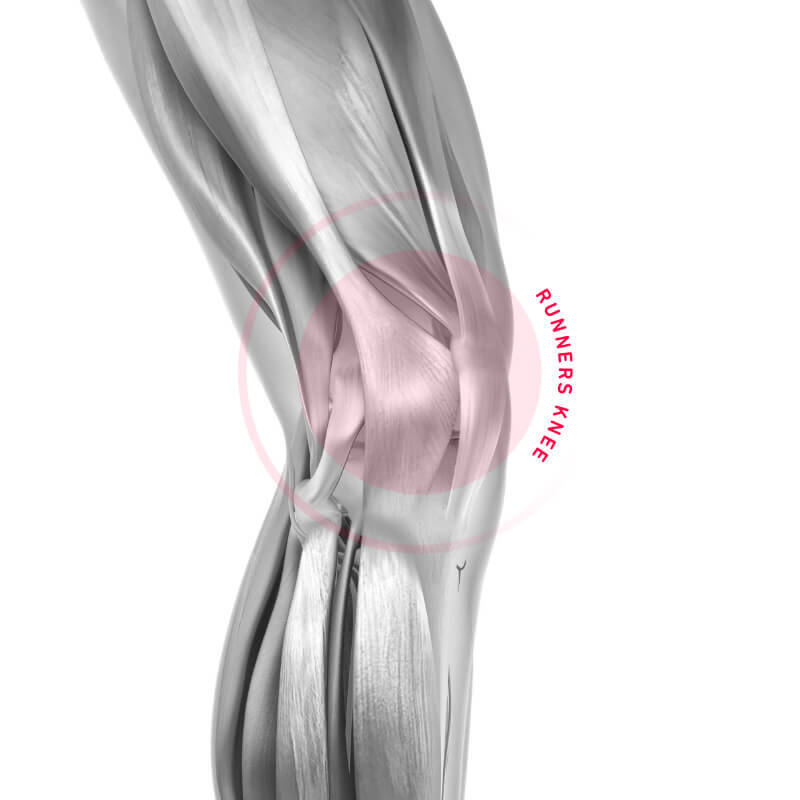

Wie genau, erfährst Du hier.Läuferknie

Das Läuferknie zählt zu den häufigsten Beschwerden bei Läufern. Hier erfährst Du alles Wichtige über Symptome, Ursachen und Therapie.